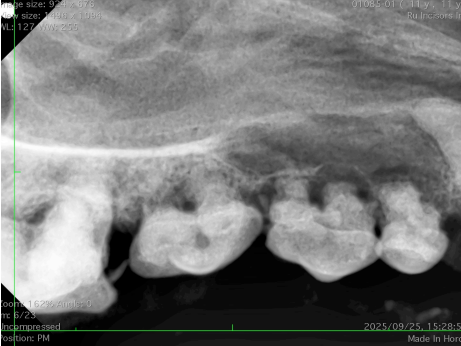

(歯科レントゲン)

歯槽骨が骨吸収され、歯根が露出している。

歯科用レントゲンにて歯根部と歯槽骨の状態を確認。